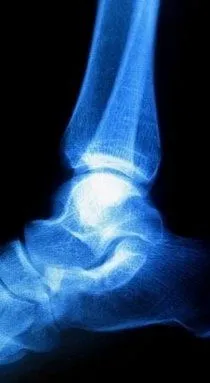

If you are suffering from Haglund's deformity you will most likely have noticed a bony enlargement at the back of the heel. This inflammation is caused when the soft tissue around the Achilles tendon becomes irritated. Irritation at this particular spot is often the result of pressure caused by the back of pump-style shoes. Other signs of Haglund's deformity include pain in the back of the heel, where the Achilles tendon and the heel meet, swelling in the back of the heel and redness or inflamed tissue at the site of the swelling.